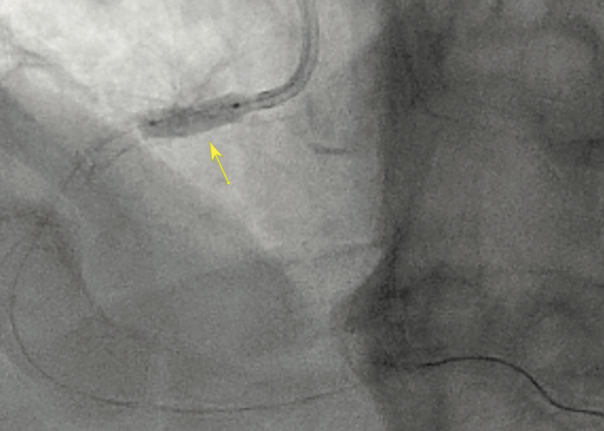

Angiography showed a severe ostial RCA stenosis with thick calcification noted on angiography and intravascular ultrasound (IVUS) showed approximately a 270° arc of calcification (Figure 1). A 4 mm x 15 mm Euphora noncompliant balloon (Medtronic) was initially used to dilate the stenosis, but was under-expanded (Figure 2). At this point, a 4 mm x 12 mm Shockwave C2 coronary intravascular lithotripsy (IVL) balloon (Shockwave Medical) was used and after 2 pulse cycles at 4 atmospheres (atm), the balloon expanded completely (Figure 3). Six more cycles of IVL pulses were performed in the same area. IVUS showed disruption in the calcification. A 4 mm x 16 mm Synergy Megatron stent (Boston Scientific) was deployed at 12 atm and a 4.5 mm Quantum Apex NC balloon (Boston Scientific) was used to post dilate at 20 mm, with good stent expansion and apposition as seen on angiography and IVUS (Figure 4). No complications were encountered and the patient was discharged later that evening in good condition.